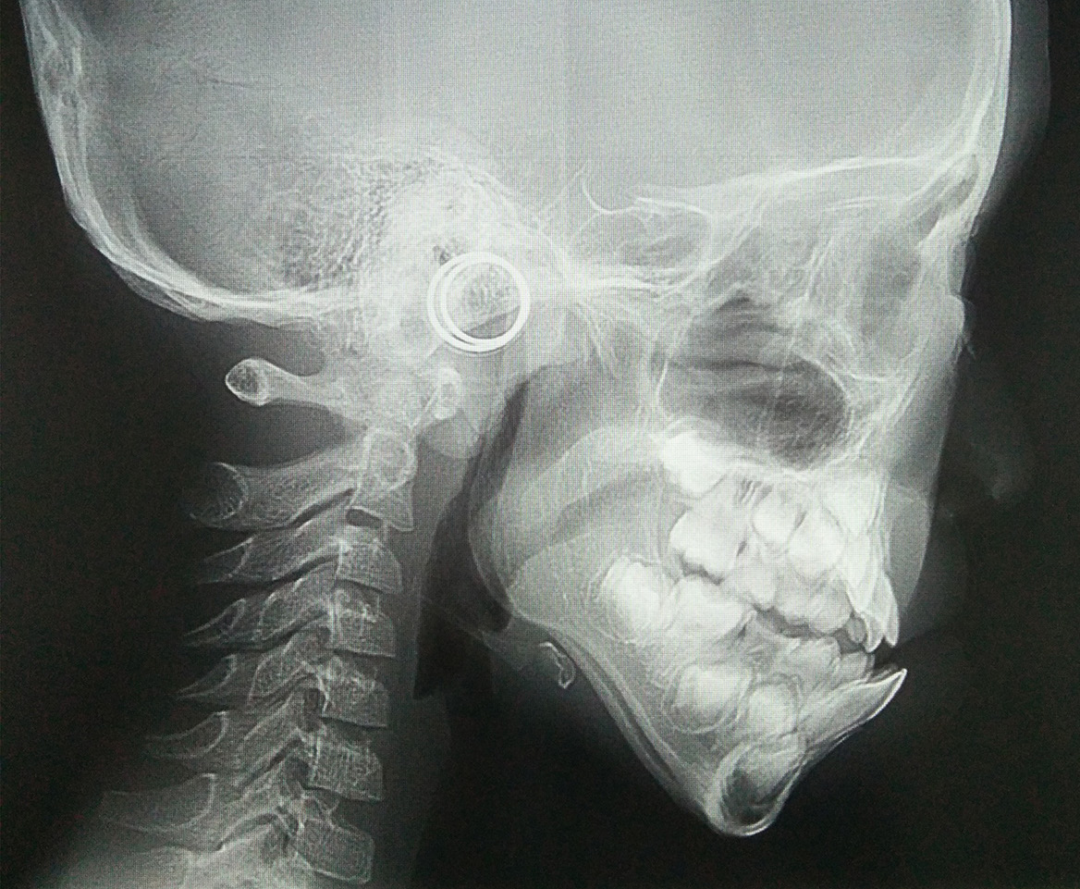

就像这个小朋友初诊检查头侧片子发现骨骼I类、牙齿III类咬合关系。但是,孩子家长拒绝接受治疗,觉得孩子换完牙就变好了,不会变成严重的地包天问题。

但是1年半之后,孩子前牙地包天问题加重,下颌前凸也很明显,这才又想要通过牙齿矫正改善孩子的牙齿咬合和面型情况。